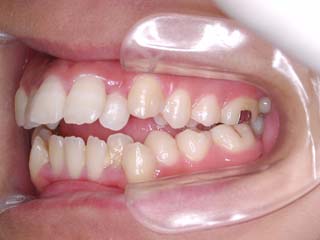

主訴:上の歯が出ている

診断名:顎関節症、上顎前突、叢生を伴う開咬

年齢:20歳

使用した主な装置名:TPB、マルチブラケット装置

抜歯/非抜歯および抜歯部位:抜歯(上顎左右第一小臼歯、下顎左右第二小臼歯)

治療期間:動的処置2年3か月、経過観察3年

費用の目安:保険適応 自己負担金として30~50万

リスク、副作用:外科手術によるリスク、マルチブラケット治療に伴う歯根吸収など偶発症が発生するリスクがある。

比較的強い叢生と、下顎の劣成長を伴う開咬が見られます。成長を終了した永久歯列ですので、骨の大きさのズレへのアプローチは大きく別れる所です。程度が小さければ、歯の傾きで補うように解決しますし、大きなズレであれば、外科的に骨のズレを改善する治療が選択されます。垂直的な問題はその他の不正咬合と比較して、解決が極めて困難な事が多いです。治療後の後戻りが頻繁に見られる不正咬合ですので、外科矯正での改善が望ましい場合も多いでしょう。

術前矯正の仕上げにスプリント治療を行った方が良い場合が多いです。現在、当院での治療では、術前に3か月のスプリント治療を必須にしております。せっかく手術までしてかみ合わせの位置を合わせようとしているのに、顎の関節の位置がずれていたらどうなるでしょう。顎の関節は往々にして顎の大きさのズレをカムフラージュするような偏位を示すので、術後にじわじわと後戻りしているような現れ方で、ズレが見えてくるのでは?このスプリント治療を徹底できたケースでは術後の安定性が極めて高いと感じています。

外科手術は、上顎のインパクションのみをLeFort1にて行いました。